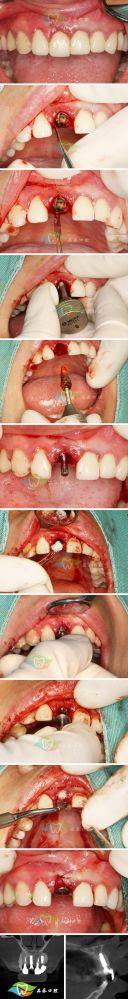

第二个擅长项目是即刻种植。即刻种植就是在拔牙后马上进行种植,这样可以节省治疗时间,减少患者的等待痛苦。高医生在即刻种植方面技术娴熟,他能够精细地把握拔牙和种植的时机,确保种植体能够顺利植入,并且与周围的组织理想融合。他就像是一位神奇的魔法师,能在短时间内为患者解决牙齿缺失的问题。

第三个技术优势是精细的操作。在进行种植手术等治疗时,高医生的操作非常精细。他会使用精良的设备和工具,严谨地定位种植体的位置和角度,确保种植的成效。他的精细操作就像一位非凡的狙击手,能够正确地命中目标,为患者带来更好的治疗成效。